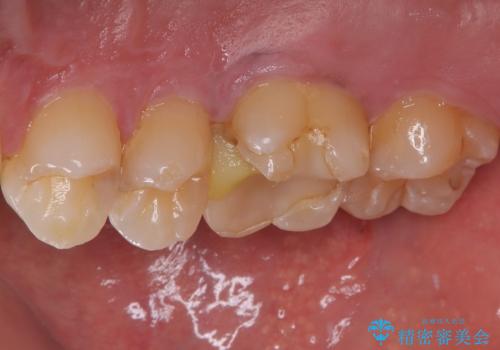

拡大鏡視野下で保険のプラスチック(コンポジットレジン)、虫歯を除去し、フルジルコニアクラウン、に適した形にしました。

歯と歯茎の間に圧排糸と呼ばれる糸を入れてシリコーン印象を行いました。